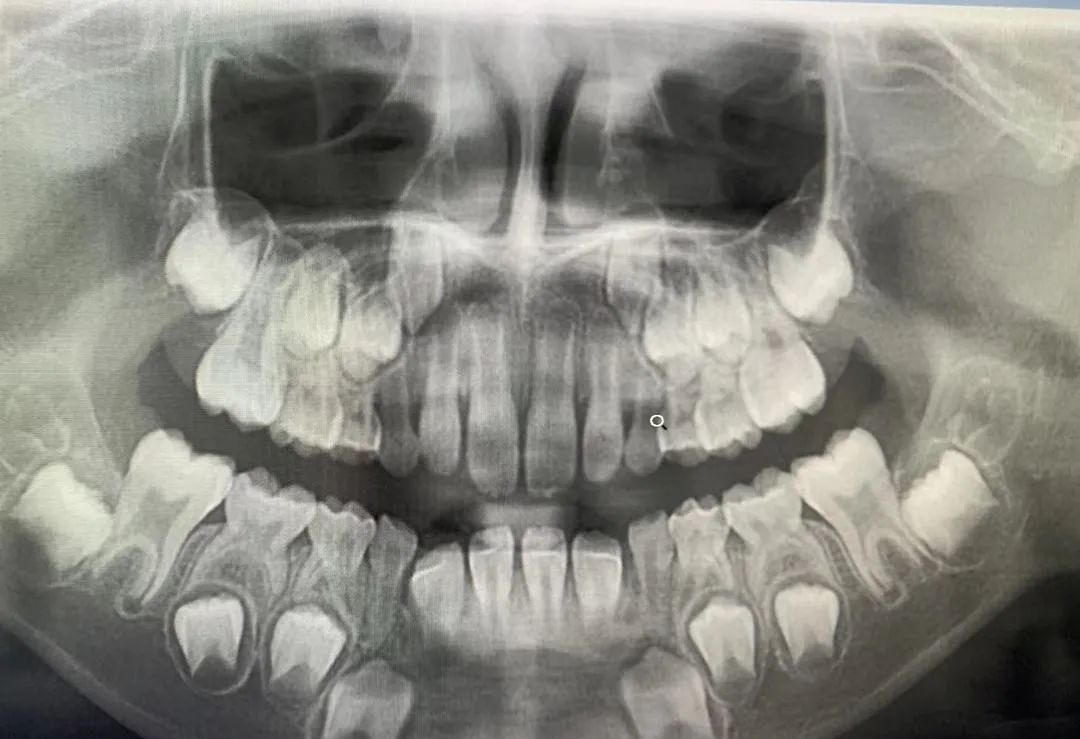

CBCT 是目前国际最先进的口腔专用CT,在业界被誉为神奇的“慧眼”,具有扫描快、范围大、精度高、应用广、辐射量低的特点。可以通过其强大软件处理功能以及面部匹配技术迅速形成清晰逼真的三维图像,较传统CT对于牙齿及颌骨组织的结构成像质量更高,彻底解决了口内牙片机、口腔全景机等口腔X射线设备影像重叠、畸变的问题,可以便捷直观地发现多种牙齿隐患问题,为口腔医生提供精准的诊断与治疗依据。

1、口腔颌面外科方面:用于肿瘤、囊肿的范围及与上颌窦及下颌神经管的关系,颌骨骨髓炎的诊断,骨折的诊断及术前指导,阻生智齿的诊断及拔除指导,多生牙及埋伏牙的定位及毗邻关系,颞下颌关节病的诊断等。

4、牙列错颌畸形矫治方面:用于研究颅面生长发育,诊断分析、矫治设计、前后对比,头影测量等。